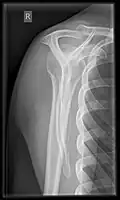

- Y-projection

The lateral contour of the shoulder should be positioned in front of the film in a way that the longitudinal axis of the scapula continues parallel to the path of the rays. This method reveals:[26]

- The horizontal centralization of the humerus head and socket

- The osseous margins of the coraco-acromial arch and hence the supraspinatus outlet canal

- The shape of the acromion

This projection has a low tolerance for errors and, accordingly, needs proper execution.[26] The Y-projection can be traced back to Wijnblath’s 1933 published cavitas-en-face projection.[27]

Y-projection conventional radiography